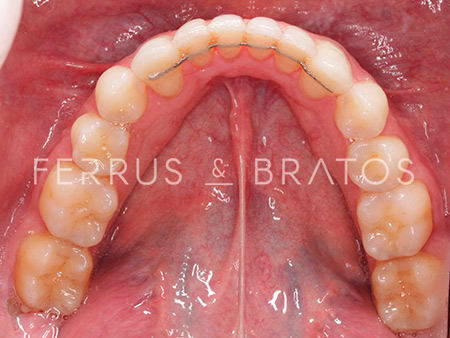

Raúl presentaba diversos problemas relacionados con su mandíbula: apiñamiento severo, una sobremordida muy aumetada y una ligera clase II dentaria. Cuando acudió a nuestra clínica, la doctora Patricia Bratos planificó un tratamiento con ortodoncia de brackets de Zafiro, un sistema muy estético y eficaz.

Una vez que corregida la alineación, la nivelación y la oclusión, la ortodoncista pautó un tratamiento estético para obtener un resultado aún más óptimo y natural. Dado que Raúl tenía tinciones en algunas piezas, la doctora recomendó un blanqueamiento tanto interno como externo para unificar el tono de la sonrisa. Ahora, Raúl nos cuenta que sonríe mucho más y con mayor confianza en sí mismo.